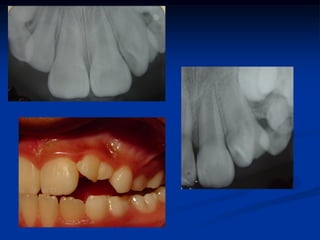

1. RX Diagnóstico

2. Indicação terapêutica

Dentes com vitalidade, cav. profunda

com ou sem exposição pulpar....jovens.

3.Proteção próximo ou sobre a polpa

4.Base CIV

5.Rx proservação

6.Restauração

1. RX Diagnóstico 2.Indicação terapêutica Dentes com vitalidade, cav. profunda com ou sem exposição pulpar....jovens. 3.Proteção próximo ou sobre a polpa 4.Base CIV 5.Rx proservação 6.Restauração